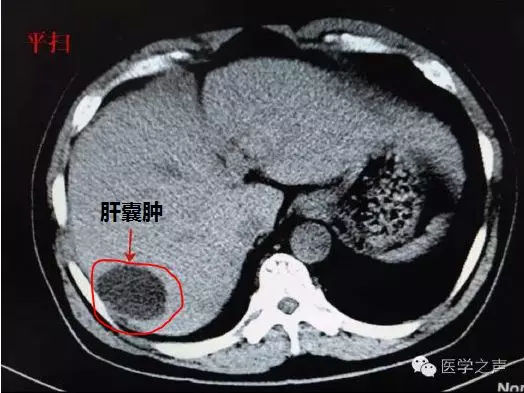

那么,得了肝囊腫是否意味著只能等死呢?接下來,我們將從最基本的醫學知識開始,消除大家對肝囊腫的疑慮。肝囊腫是一種常見的良性肝臟疾病,它主要由肝臟內部的囊性擴張所形成,肝囊腫可以是單個的,也可以是多個的。

肝囊腫是一種比較常見的疾病,平均每20個人中就有一個人患有肝囊腫。肝囊腫分為先天性肝囊腫和獲得性肝囊腫。常見的手術方法有囊腫開窗術或去頂術,多在腹腔鏡下完成該手術。很多人在體檢時發現自己患有肝囊腫,因此感到緊張和焦慮。

大多數肝囊腫是無癥狀的,通常是在進行影像檢查時無意中發現。02肝臟損傷肝臟受到損傷或創傷后,修復過程中可能有囊腫形成。但是,少數肝囊腫可能是囊腺癌或寄生蟲的表現,通常會伴隨其他相應的臨床癥狀。

總之,對于大多數檢查中發現的肝囊腫,不必過于擔心,只需要定期隨訪,其余時間忽略它們的存在即可。02手術切除對于較大的、癥狀明顯的囊腫或復雜的囊腫,必要時進行手術切除,效果確切,復發少。